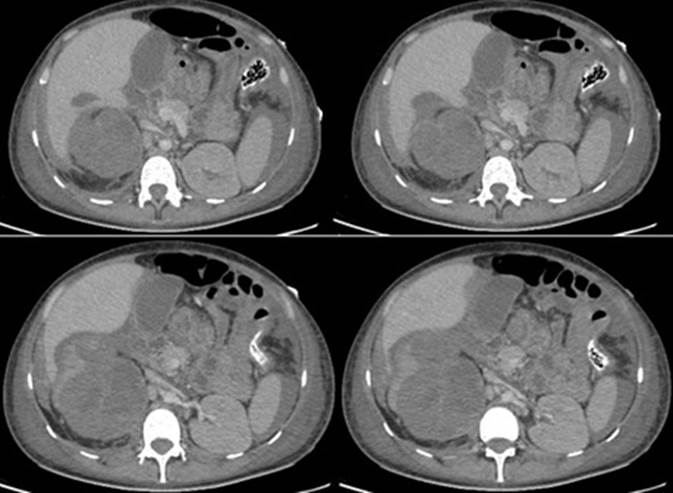

Durante su estancia se observó reactantes de fase aguda en aumento, conservación función renal, hemograma con leucocitosis y neutrofilia, anemia moderada hipocrómica, microcítica escalonando esquema de antibioticoterapia. En su día 5 de hospitalización presenta choque hemodinámico, amenización severa aguda, insuficiencia respiratoria aguda severa con requerimiento de UCI y soporte ventilatorio, inotrópico y transfusión hemoderivados, con impresión diagnostico en tomografía computarizada de abdomen y pelvis de laceración del polo superior del riñón derecho con hematoma en el espacio pararenal anterior y sangrado activo, contusión hepática en el segmento VI (Figura 1 y Figura 2), cambios pielonefritis xantogranulomatosa derecha, dilatación urotelial a nivel de la pelvis renal y uréter derecho y engrosamiento vesical ya conocido por reporte histopatológico. Se traslada a quirófanos para laparotomía exploratoria encontrando hemoperitoneo de 3000cc aproximadamente, perforación de fascia de gerota anterior derecha hacia el polo renal superior derecho, nefromegalia derecha 15cm, pionefrosis y riñón de apariencia cianótica no viable con abundante tejido inflamatorio por lo cual se realiza nefrectomía simple.